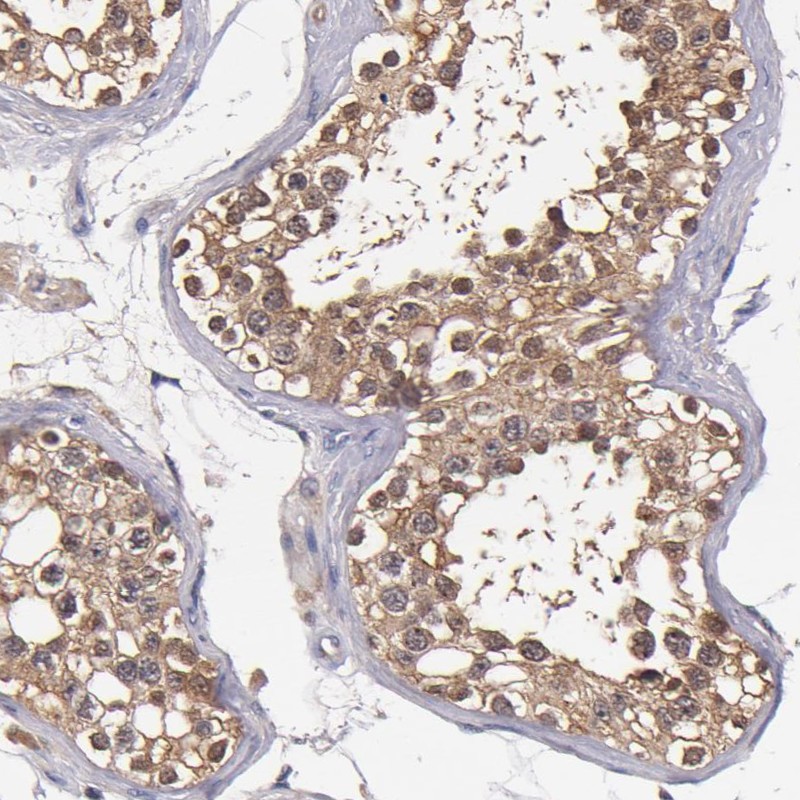

Immunohistochemical staining of human testis shows moderate cytoplasmic positivity in cells in seminiferous ducts.